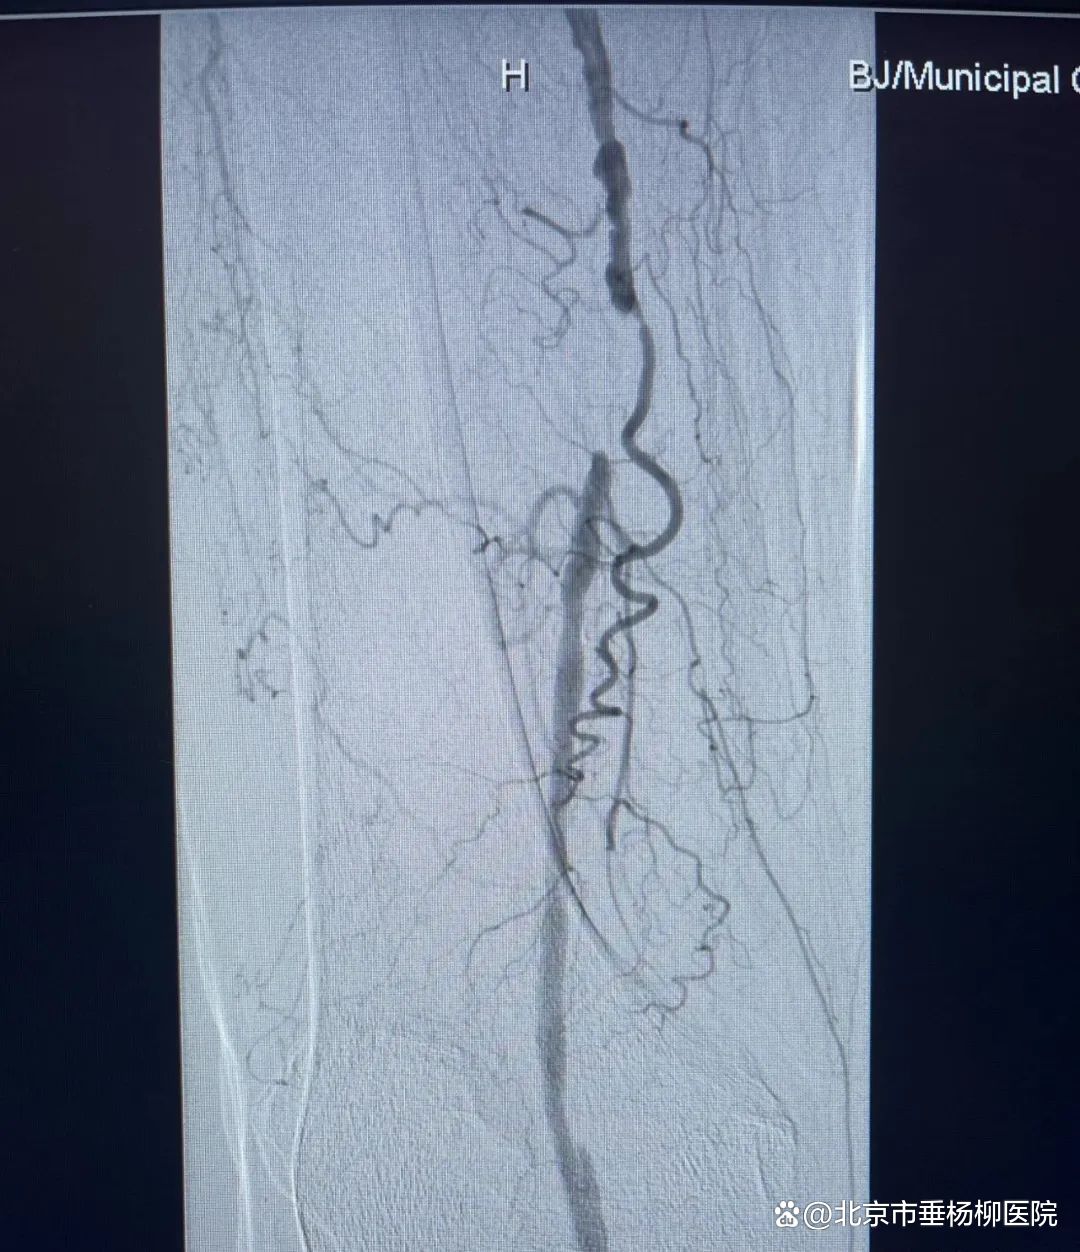

北京市垂杨柳医院介入与血管外科主任杨永久团队凭借丰富的经验和精湛的技术,为胡奶奶实施了微创手术。术前,团队进行了仔细的评估和周密的准备,确保手术的安全性和有效性。术中,他们通过微创手段在血管病变段放置球囊进行扩张,并植入支架,成功恢复了血管的通畅。这一手术的成功不仅让胡女士重新站了起来,更让她对未来充满了信心。同时,也展示了微创手术在超高龄患者下肢动脉治疗中的巨大潜力。